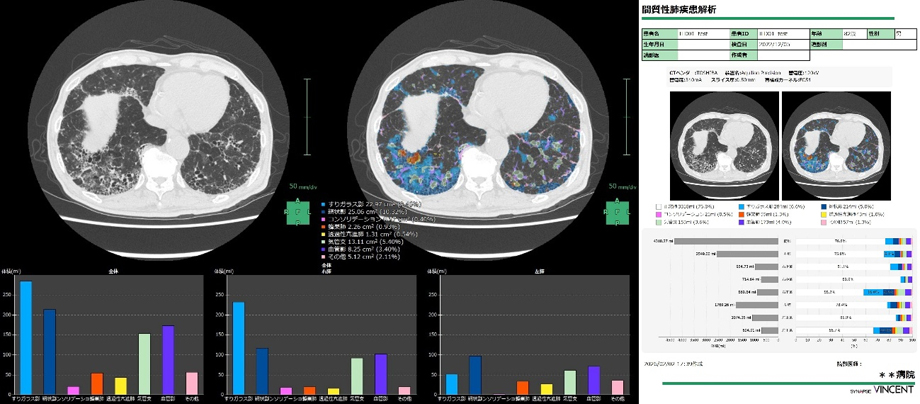

脳区域解析や間質性肺疾患解析においても医療現場のニーズに対応し、セグメンテーションした領域の定量化とレポート作成機能を新たに搭載した。幅広いシーンで活用できる3Dワークステーションとして、アップデートしている。

2025年にリリースした間質性肺疾患解析*6にも新たにレポート機能を搭載し、CT画像から定量評価した結果をレポートとしてアウトプットする一連のフローを「SYNAPSE VINCENT」で行うことができるようになる。